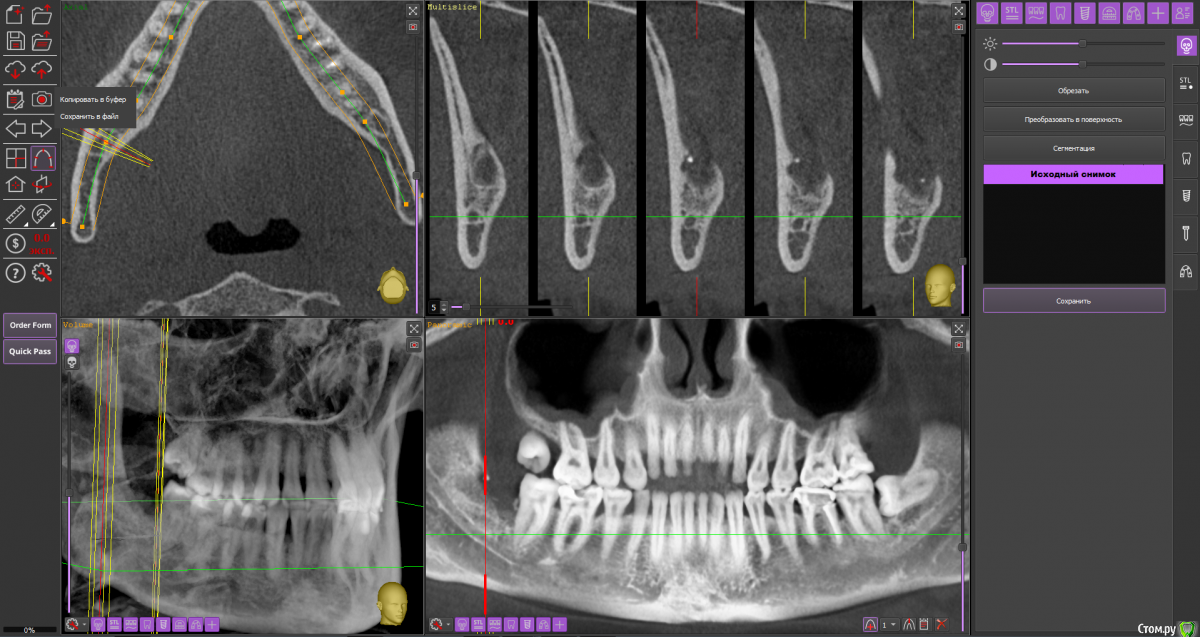

Спилка Опубликовано 15 октября, 2020 Поделиться Опубликовано 15 октября, 2020 В августе решилась на удаление нижних зубов мудрости (38 и 48). Врач - стоматолог-хирург посоветовала не удалять сразу оба, а по-очереди и начать с 48 зуба, ретинированного, дистопированного, возле которого больший очаг воспаления.В процессе удаления был сделан укол анестезии, потом разрезана десна, отпилена коронка зуба, упиравшаяся в соседнюю “семерку” - 47 зуб, и удалён корень, далее рана была зашита. В день операции прицельных снимков ни до, ни после не делали, врач руководствовалась КТ месячной давности, лунка после удаления не промывалась, лекарство, дренаж не ставились.Процесс удаления зуба прошел, на мой взгляд, быстро, дёргано, врач сразу же ушла после завершения, была не в настроении, явно чем-то обеспокоена. На свой счет я это не приняла, но осадок остался.Назначения врача в плане приема таблеток: нимесил, супрастин, амоксиклав, холод первые суткиАнтибиотик, в отличие от прочих назначений, был рекомендован при наличии болей на третий день после удаления.Меня предупредили, что операция сложная, “помучаюсь” с заживлением и восстановлением.Дома первые сутки прикладывала холод, пила нимесил и супрастин по нормам назначения.На третьи сутки супруг заметил, что изо рта стало “плохо пахнуть”, “гнилостно”, позвонил врачу, она сказала, что на третий день отёк самый большой, это норма, и посоветовала начать пить антибиотик, и если будет так же или лучше, все ок, если хуже - приехать на приём, лунку вскроют, заново сформируют сгусток и зашьют.На четвертые сутки после удаления ситуация ухудшилась, было принято решение показаться в областную клинику хирургу. В приемном отделении, увидев мою щеку, погоняли по кабинетам, взяли анализы, сделали рентген, КТ, ЭКГ, еще что-то - уже не помню, и …..поставили диагноз - флегмона околочелюстной области справа. И экстренно прооперировали. Подробности описывать не буду, жутко все это, никому не пожелаю... 11 дней в стационаре, выписали с открытой раной на амбулаторное лечение к хирургу по месту жительства.Я всю жизнь по стоматологам, много разных сменила, читаю информацию, что-то понимаю, но все же я не специалист. Эта клиника самая лучшая и дорогая в области, думала уж там все будет отлично. Но пока лечилась в областном стационаре, много читала и возникли сомнения, что удаление произведено отлично.После того, как рана затянулась, попытались прояснить этот вопрос с клиникой, где удаляли зуб. Там сказали, что я не добросовестный пациент, что никаких установленных нормативов, протоколов лечения не существует, соответственно, врач ничего не мог нарушить при проведении операции по удалению 48 зуба, попугали стоимостью экспертизы. И вообще, после вмешательства врачей областной клиники уже доказать ничего нельзя, засомневались в верности диагноза - флегмона околочелюстной области справа. По мнению директора клиники и глав врача удаление проведено идеально - они смотрели записи камеры наблюдения.Собственно - вопрос в чем - может они правы и удаление действительно прошло “идеально” - как они утверждают, и флегмоны не было.У меня есть 3Д снимки за месяц до удаления и через полтора месяца после. Как могла в программе выставила диапазоны, сделала снимки экрана. И кажется мне, что там осколки зуба в лунке… Муж сделал фото лунки - по-моему осколок видно.Я в растерянности, если клиника отработала идеально, почему такие катастрофические последствия?!! Если так можно - оцените ситуацию в целом, так как теряюсь сформулировать какой-то конкретный вопрос. Заранее спасибо всем! Ссылка на комментарий

Спилка Опубликовано 15 октября, 2020 Автор Поделиться Опубликовано 15 октября, 2020 Загрузите кт на файлообменникhttps://yadi.sk/d/cU-dxQlKtbsNfQКЛКТ И фото места где был зуб Ссылка на комментарий

Irouil Опубликовано 16 октября, 2020 Поделиться Опубликовано 16 октября, 2020 Вот именно мнение клиницистов меня и интересует, насколько правильно меня лечилиИменно это сказать клиницист не может в принципе, такие заключения даются на экспертизе врачом-экспертомКакой результат по вашему достигнут в стационаре, не подохла?Я бы выразился иначе, но суть Вы передали верно: главная цель лечения пациентов в экстренной медицине (а инфекционные воспалительные процессы, в первую очередь флегмоны, в челюстно-лицевой области являются показанием именно для применения такого вида лечения) - спасение жизни, ибо угроза для нее была. Теперь по существу Во-первых я не вижу на предоставленной компьютерной томограмме потенциально инфицированных фрагментов, угрожающих Вашему здоровью. И расскажите подробнее про губу - отмечается ее онемение? Сможете обрисовать карандашом область онемения и сделать фото? Ссылка на комментарий

Zlata-doctor Опубликовано 17 октября, 2020 Поделиться Опубликовано 17 октября, 2020 (изменено) Я не вижу никаких осколков на представленных снимках. Замечу, даже если бы они там и были, это не может являться причиной флегмоны. Патофизиология данного процесса гораздо более сложна и связана также с особенностями флоры вашей полости рта, вашего иммунитета, с непростой анатомией данной области, сложностью удаления и другими факторами. И таки да, околочелюстной области как анатомического образования, не существует. Промывание, введение лексредств и дренирование проводятся врачом по показаниям, он не должен 100% это сделать, а иногда это и нежелательно. Также хочу Вам сказать, что здесь собрались врачи, которые абсолютно бесплатно в рамках своей компетенции пытаются помогать вам, пациентам. И никакая это не цеховая солидарность, просто проводить экспертизу и ставить вердикт на расстоянии, не имея полной задокументированной истории вашей болезни-непрофессионально, преступно и аморально. К сожалению, люди сейчас воспитаны на скандальных ТВ роликах, где диагнозы обвинения, а заодно и приговор раздаются на раз-два. Здесь такого горлопанства в погоне за сенсацией не будет. Мы вам очень сочувствуем и желаем скорейшего выздоровления. Изменено 17 октября, 2020 пользователем Zlata-doctor 5 Ссылка на комментарий